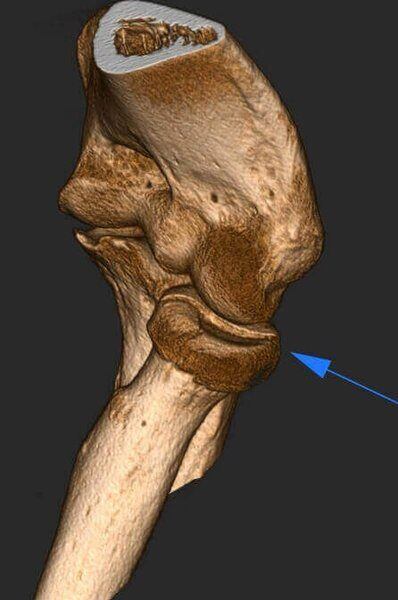

- Fractura de capítulo y tróclea con medio de osteosíntesis

Fractura de escafoides con material de osteosíntesis.